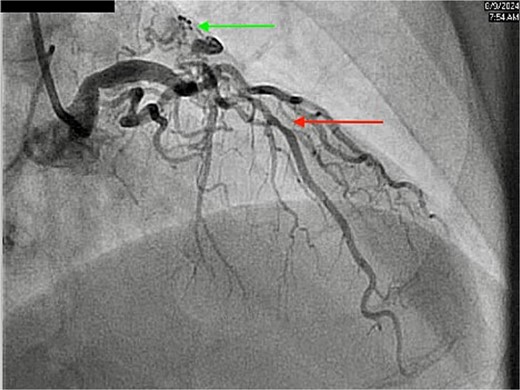

The CCTA revealed a well-developed CPF originating from the proximal LAD (Fig. 1), with moderate stenosis (50–70%) in the proximal LAD. The patient’s total coronary artery calcium score (Agatston score) was 672, indicative of advanced coronary atherosclerosis. Coronary angiography confirmed a diffuse 60% stenosis in the ostial and mid LAD, with mild luminal irregularities (<20%) in the left main coronary artery and right coronary artery (RCA). It also redemonstrated the presence of proximal LAD to pulmonary artery fistula (Fig. 2). No significant oxygen saturation step-up was observed, indicating the absence of a hemodynamically significant shunt.

Coronary angiography showing diffuse stenosis in the LAD (red arrow) and CPF (green arrow).